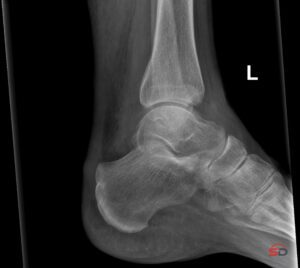

1. Röntgen

Das konventionelle Röntgen bleibt die erste Stufe in der Akutdiagnostik. Es dient vor allem dem Ausschluss eindeutiger Frakturen und Luxationen. Die Sensitivität für okkulte Frakturen ist jedoch limitiert, insbesondere bei nicht dislozierten intraartikulären Läsionen und reinen Impressionsverletzungen.

Trotz hoher Verfügbarkeit und guter räumlicher Auflösung kann das Röntgen subtile intraossäre Schäden nicht zuverlässig darstellen. Besonders problematisch ist, dass sich die Veränderungen häufig auf die trabekuläre Spongiosa beschränken und die Kortikalis äußerlich intakt bleibt.

Hinzu kommen Überlagerungseffekte in Gelenknähe und die begrenzte Anzahl an Projektionen. Eine nicht dislozierte Fraktur kann so leicht „zwischen den Ebenen“ liegen und bleibt radiologisch unentdeckt.